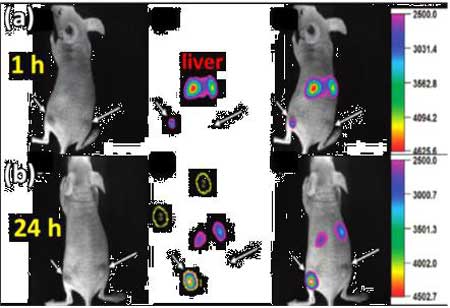

上转换发光纳米材料(UCNPs)具有荧光寿命长、潜在生物毒性低、穿透深度大、对生物组织损伤小且几乎没有背景光等显著优点,近年来在生物成像及生物检测等领域已经得到广泛应用,下图未上转换纳米颗粒在生物活体中进行肿瘤标记。

Figure 5.上转换纳米材料在肿瘤靶向成像中的应用1